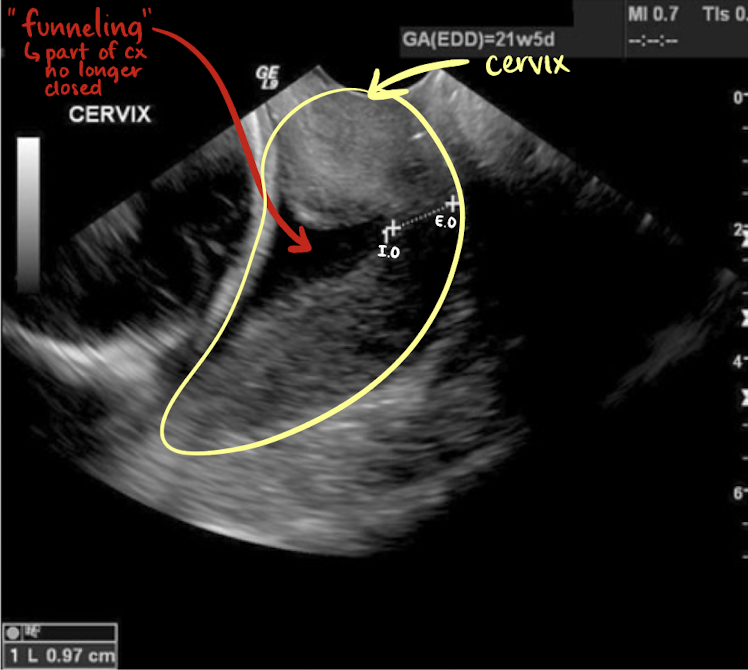

cervical length

CL = distance between internal os and external cervical os

normal length (gravid uterus) is at least 3 cm

cervical incompetence is CL less than 2.5 cm

short CL is marker for increased preterm birth loss

risk of loss inverselt proportional to CL

what is cervical incompetence

when CL is less than 2.5 cm

cervix does not remain closed

is this normal or cervical incompetence?

incompetence